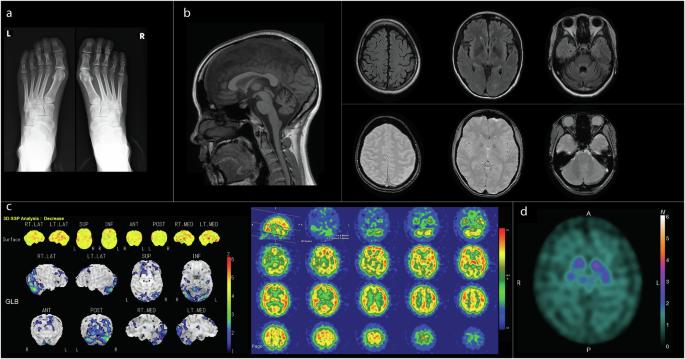

PLA2G6-associated neurodegeneration (PLAN) encompasses a spectrum of phenotypes caused by biallelic pathogenic variants in PLA2G6. Initially linked to infantile and atypical neuroaxonal dystrophy, PLAN now includes adult-onset conditions such as dystonia-parkinsonism, ataxia, and spastic paraplegia. We report a female patient presenting young-onset parkinsonism with pyramidal tract signs, cerebellar atrophy, and autonomic dysfunction, mimicking multiple system atrophy (MSA). Neuroimaging showed decreased dopamine uptake and cerebellar hypoperfusion. Genetic analysis identified a homozygous pathogenic variant in PLA2G6 (c.967G>A, p.Val323Met), confirming a diagnosis of PLAN. Interestingly, elevated serum autotaxin levels (4.67 ng/mL) without liver abnormalities. Bilateral brachymetatarsia was also observed, which may indicate an association with the PLA2G6 variant. This case underscores the importance of considering PLAN in cases of young-onset parkinsonism with multisystem involvement. Genetic testing is crucial for accurate diagnosis and management of such cases. Elevated serum autotaxin levels may be associated with decreased phospholipase activity in PLAN and warrants further investigation.